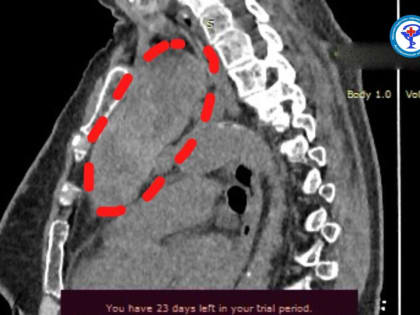

Их опыт высоко оценили зарубежные эксперты В Астраханском онкодиспансере мультидисциплинарная бригада успешно провела операцию по удалению огромной опухоли у 73-летней пациентки.